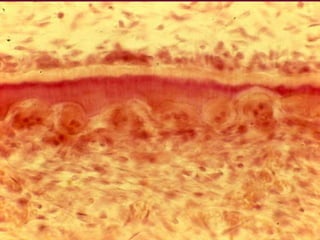

Intermittent resorption

During root resorption,

periods of resorption

are alternated by

periods of cementum

repair.

Cementoblasts

deposit cementum in

areas of resorption

forming a reversal

line. Some

become embedded in

the cementum and

are then called

Cementocytes.

A, Reversal line; B, Cementoblasts; C,

Cementocyte.